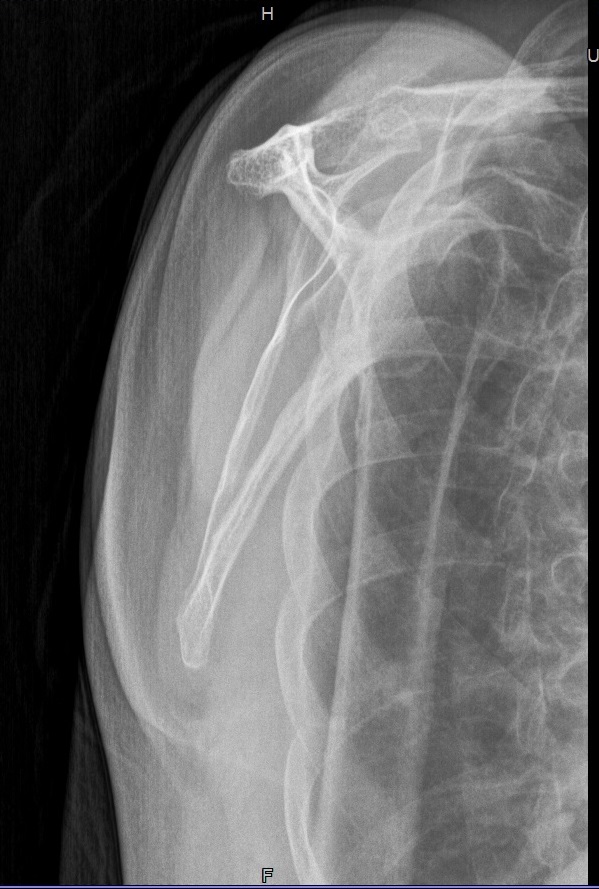

Schulter a.p.

22_2.jpg

Fehler

Hier erfolgte eine ungenügende Rotation in der Schulter, so dass das Gelenk nicht frei dargestellt wurde.

Abhilfe

Abhilfe bringt eine weitere Drehung des Patienten nach dorsal.